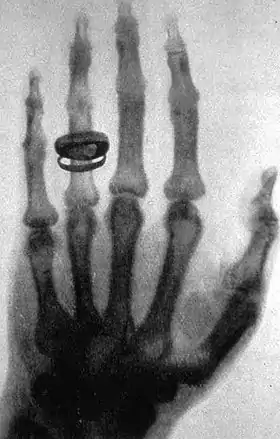

An X-ray picture (radiograph), taken by Wilhelm Röntgen, of his wife's hand

- X-rays. A form of electromagnetic radiation with a wavelength in the range of 10 to 0.01 nanometers, corresponding to frequencies in the range 30 to 3000 PHz (1015 hertz). X-rays are primarily used for diagnostic medical and industrial imaging as well as crystallography. X-rays are a form of ionizing radiation and as such can be dangerous.